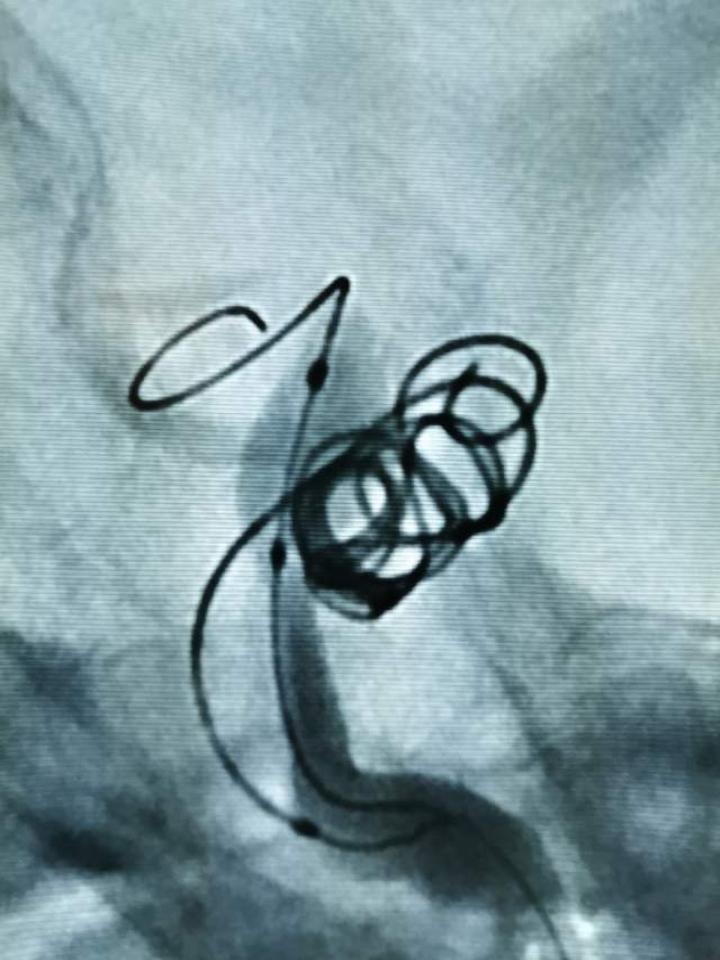

创伤性颈动脉海绵窦瘘的微创介入治疗

创伤性颈动脉海绵窦瘘患者由于外伤导致颈动脉的破口血液进入海绵窦,导致眼球突出、球结膜充血水肿、视力下降、复视等一类综合征

结论:球囊辅助下采用弹簧圈结合ONYX胶治疗TCCF简单、可靠、有效